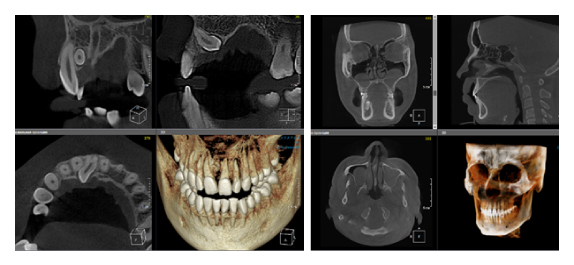

По сути воксель – это структурная единица изображения. Компьютерная томограмма состоит из вокселей, и их размер определяет качество снимка. Как правило, чем меньше FOV снимка, тем меньше и размер вокселя, а это, в свою очередь, делает изображение более качественным (рис. 3). Разные фирмы, производящие дентальные томографы пытаются конкурировать в размерах вокселя, особенно при больших зонах сканирования. Я стараюсь использовать два режима, как правило, это standart definition со средним размером вокселя и high definition с уменьшенным размером вокселя. Если намечается сложная эндодонтия, то, безусловно, high definition с минимальным значением вокселя будет крайне эффективно, но если у пациента огромное количество металла (циркон, металлокерамика и прочее) то порой именно стандартный размер вокселя помогает снизить количество артефактов и сделать изображение более читабельным.

Рис. 3. КЛКТ с зоной сканирования 5x5 см и размером вокселя 70 микрон.